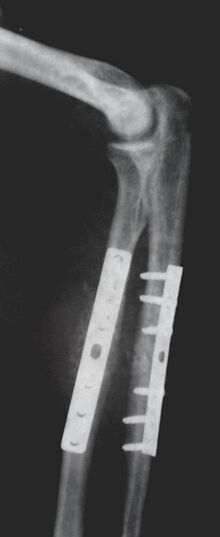

Orthopedic implants to repair fractures to the radius and ulna. Note the visible break in the ulna. (right forearm)

Orthopaedic implants help alleviate issues with the bones and joints of the body.[7] They are used to treat bone fractures, osteoarthritis, scoliosis, spinal stenosis, and chronic pain. Examples include a wide variety of pins, rods, screws, and plates used to anchor fractured bones while they heal.[3][5][6]